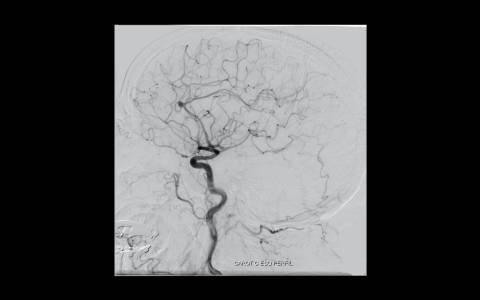

Realizado angiografia cerebral e reconstrução 3D sendo evidenciado um aneurisma de colo largo com ramo frontal emergindo do colo do aneurisma. Baseado nessas característica, foi optado por tratamento com stent redirecionado de fluxo Fred Jr., associado a micromolas de platina devido o importante inflow do ramo frontal.

Feito duplo acesso femoral e cateterismo da carótida esquerda, seguido de microcateterismo distal ao aneurisma com Headway 21 para o implante do stent, bem como do saco aneurismático para a deposição das micromolas.

Implantado um stent 2,5 x 18mm conforme programação 3D. O procedimento transcorreu sem intercorrência, mantendo a patência dos vasos envolvidos.